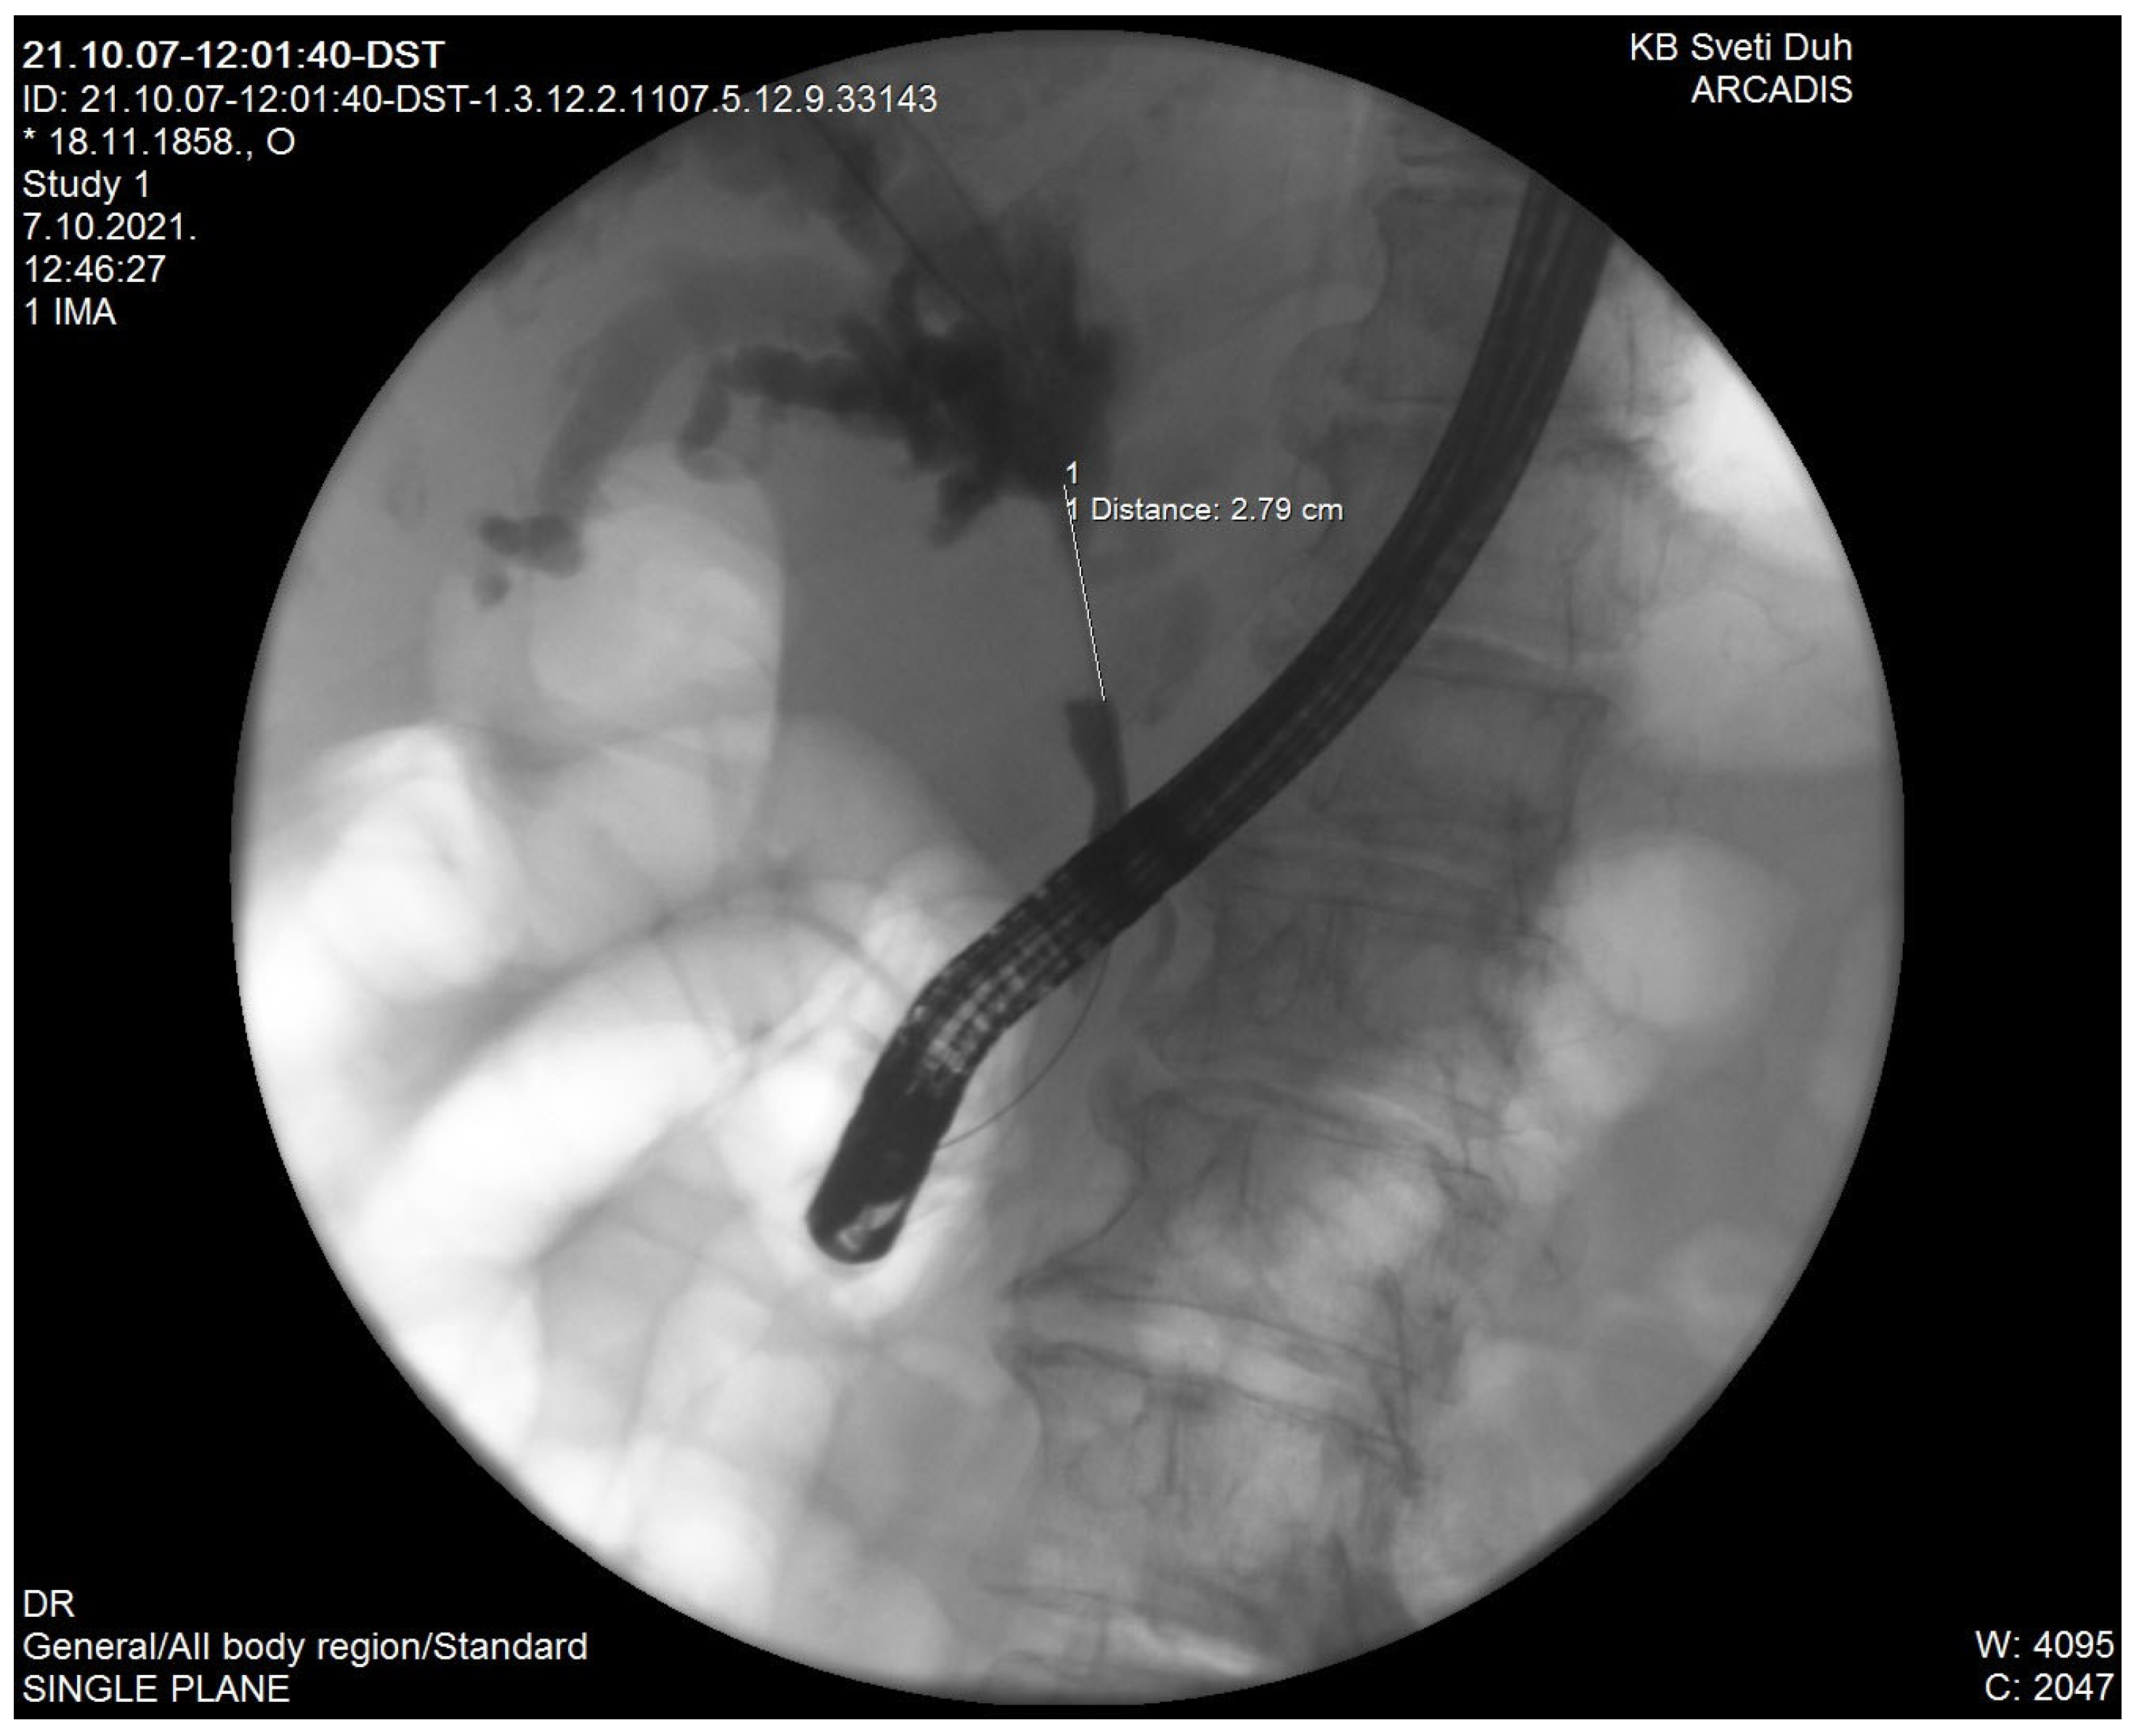

2. Recurrent Pyogenic Cholangitis